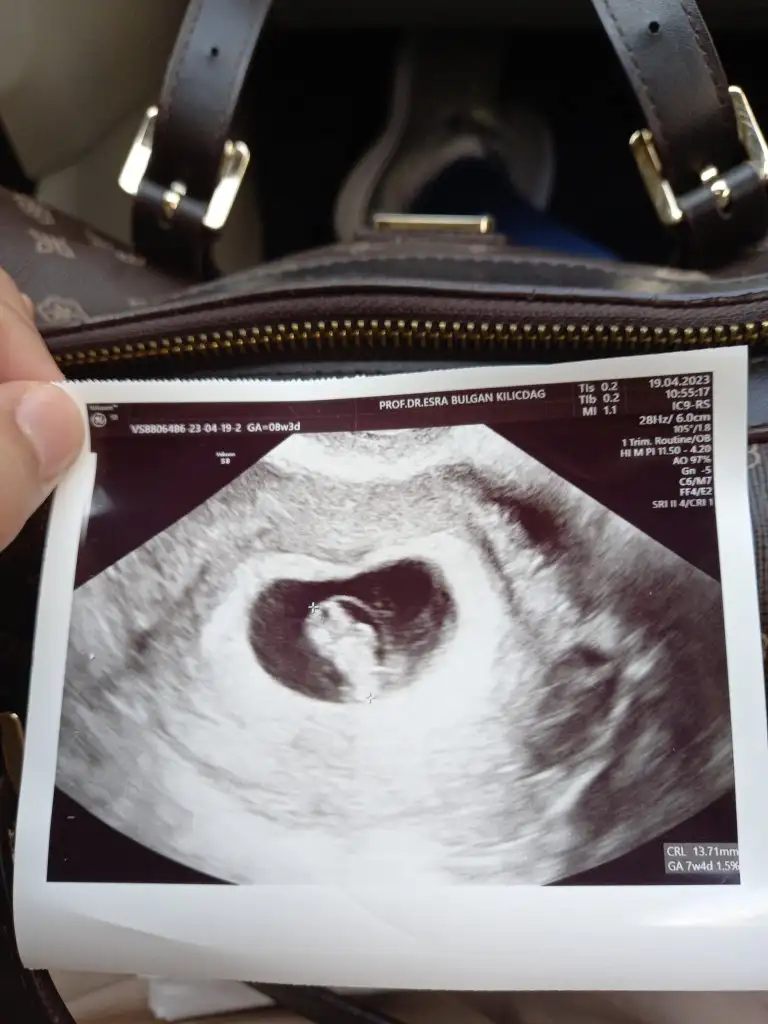

Bu çocuk ayakta mi duruyor yav dimdik hahahKızlar 6+6 karından ultrason yorumlarmısınız

En deneyimli1ciftyesilgozz ama bu görüntüde bana da çok ortada geldi bebek. Ama ben de erkek gibi hissettim

Raporda kardiyak hareket yok kese var rahim ağzı kapalı filan diyor. Kalp atışı için 5+6yım zaten ama bilmiyorum ki. Aklım karıştı gerçektenAyrıntılı ultrason da ki doktor ne dedi genelde yanılmamaları gerekmez mi evet bi tuaf olmui bu durum sen yinede doktorun dediklerini uygula canım bekle haftaya umarım güzel haber alırsın